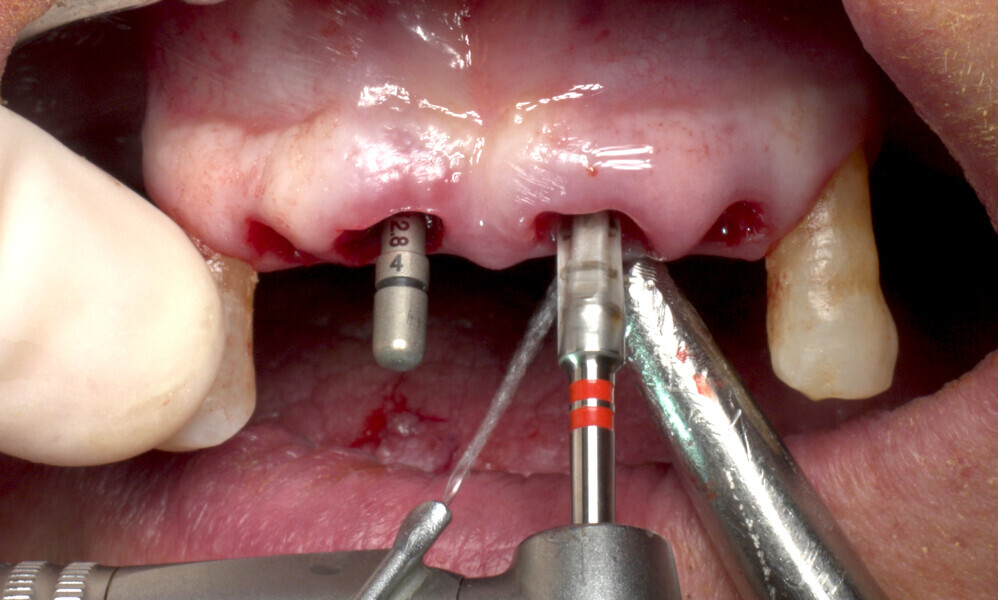

The fully digital Pro Arch protocol